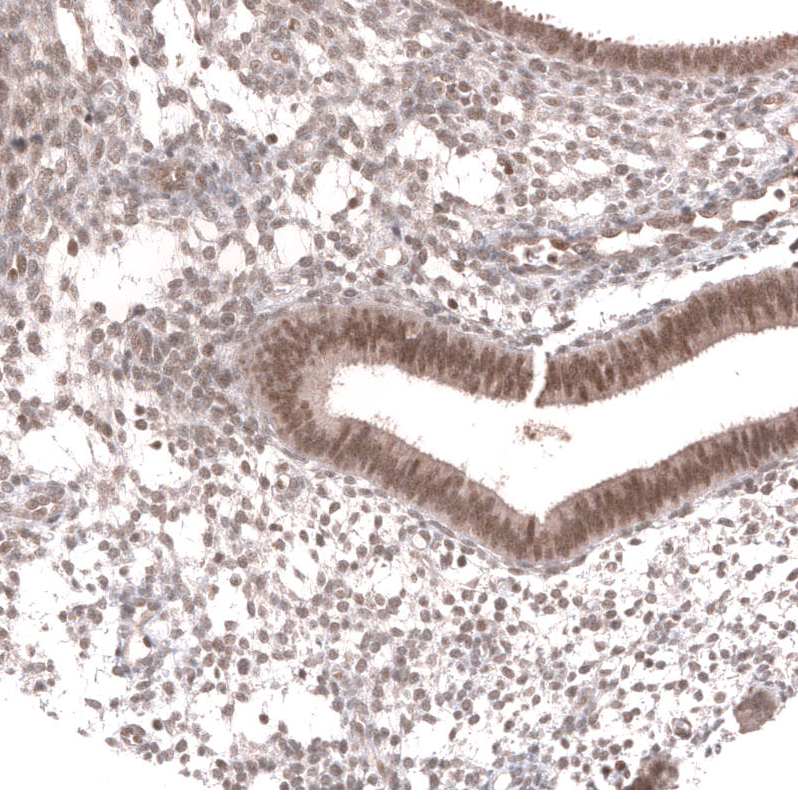

Immunohistochemical staining of human cervical cancer shows strong nuclear positivity in tumor cells.